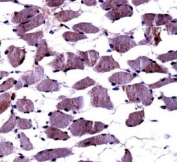

TrkA antibody immunohistochemistry analysis in formalin fixed and paraffin embedded human skeletal muscle.